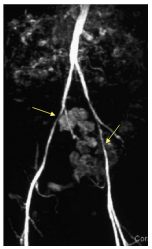

Ces techniques non invasives permettent une cartographie préthérapeutique souvent suffisante pour envisager un geste de revascularisation endovasculaire ou chirurgicale (figures 38.1 à 38.3). Les deux techniques ne nécessitent pas de ponction artérielle et l’angio-IRM ne nécessite pas d’exposition aux rayons X, ni l’utilisation de produits de contraste iodés.

Fig. 38.1 Exemple de sténose bilatérale de l’artère iliaque externe en angio-IRM des membres inférieurs.

Source : CERF, CNEBMN, 2022.

Les techniques d’angio-IRM (cf. figures 38.1 et 38.2) ou d’angioscanner (cf. figure 38.3) mettent en évidence des sténoses ou des occlusions artérielles ainsi que le développement de voies de dérivation pour compenser l’hypoperfusion en aval.

Les différences entre les deux sont les suivantes :

- les calcifications artérielles ne sont pas visualisables en IRM ;

- l’angio-IRM a tendance à légèrement surestimer les degrés de sténose ;

- les plaques athéromateuses sont parfois mieux analysées en angioscanner grâce aux reconstructions dans l’axe des vaisseaux.